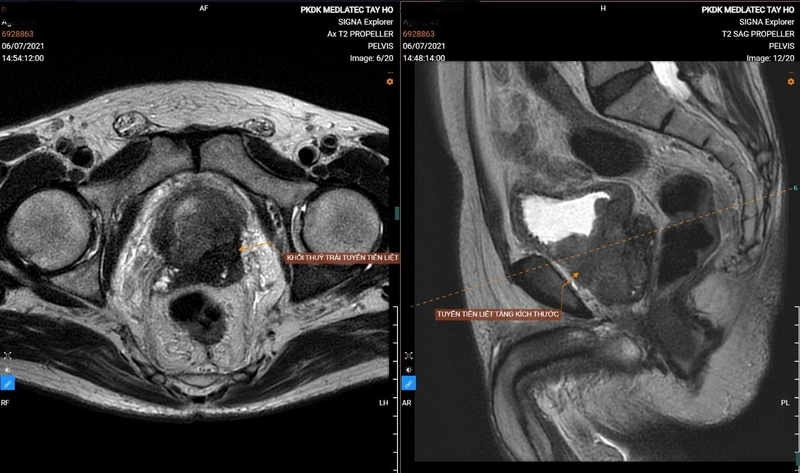

Chụp MRI tiểu khung hay còn gọi là vùng chậu được sử dụng để phát hiện các dấu hiệu bệnh lý và sự phát triển của ung thư vùng chậu trong quá trình điều trị. Sau khi chụp MRI, bác sĩ có thể phân loại và đánh giá các giai đoạn ung thư của bạn, cho phép bạn lập kế hoạch điều trị hiệu quả cho từng giai đoạn của bệnh.

Vai trò quan trọng nhất của chụp MRI tiểu khung là phát hiện sớm các tổn thương tiền ung thư. Đây là bước đầu tiên trong việc phát hiện ung thư và quyết định tỷ lệ điều trị của bệnh nhân. Tuy nhiên, bệnh nhân ung thư ở giai đoạn này thường không có dấu hiệu rõ ràng. Vì vậy, bệnh nhân thường bỏ lỡ thời điểm vàng để phát hiện ung thư sớm và điều trị hiệu quả. Chụp MRI tiểu khung giúp phát hiện những bất thường trong cơ thể như tử cung, buồng trứng, tuyến tiền liệt và cơ quan sinh sản.

Nhiệm vụ thứ hai của chụp MRI tiểu khung là đánh giá tình trạng hiện tại của khối u. Sự phát triển và xâm lấn của khối u ảnh hưởng đến các tế bào xung quanh khu vực ung thư và quan trọng nhất là xác định giai đoạn ung thư. Nhờ hình ảnh MRI, bác sĩ có thể chẩn đoán bệnh, hiểu được các giai đoạn vàng của điều trị, đưa ra hướng dẫn điều trị hiệu quả và theo dõi tiến triển tiếp theo.